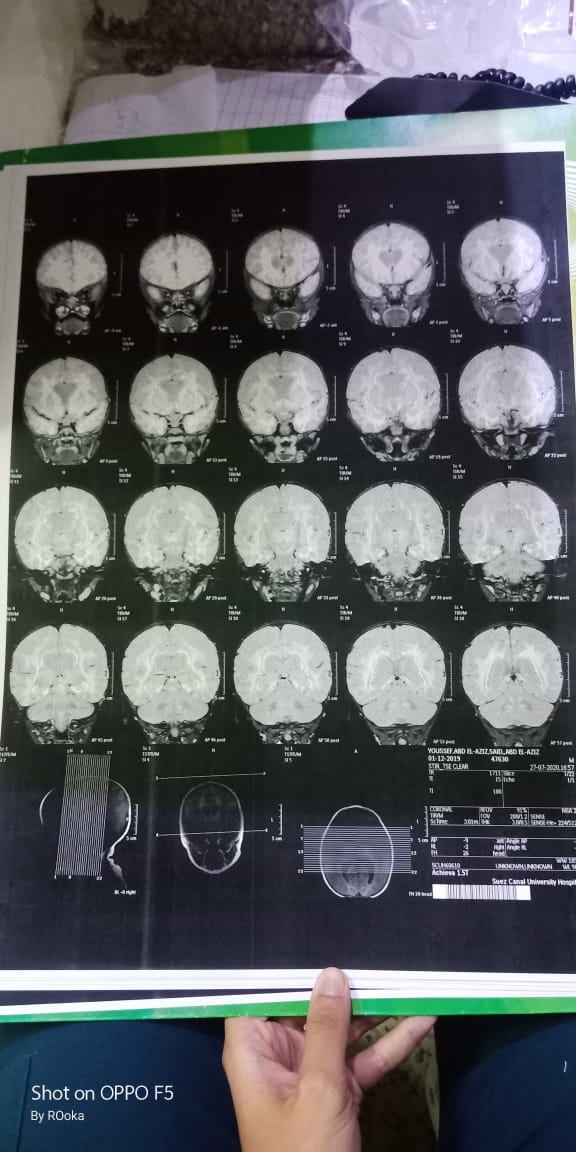

وأضاف عبد العزيز، في تصريحات خاصة لـ القاهرة 24: اكتشفنا مرض يوسف وهو عنده 6 شهور، طلع عنده نقص في المادة البيضاء، ونقص في الأكسجين، مع تآكل في القشرة المخية.

وأكد أن طفله فاقد للحركة والكلام حاليًا، مع تمدد حجم الدماغ، نتيجة معاناته من اختلالات عصبية، التي تنشأ عن المرض، معقبًا: الطفل يحتاج لجهاز طبي يساعد على تخفيف حدة الأعراض، وفقًا لاستشارة الأطباء.